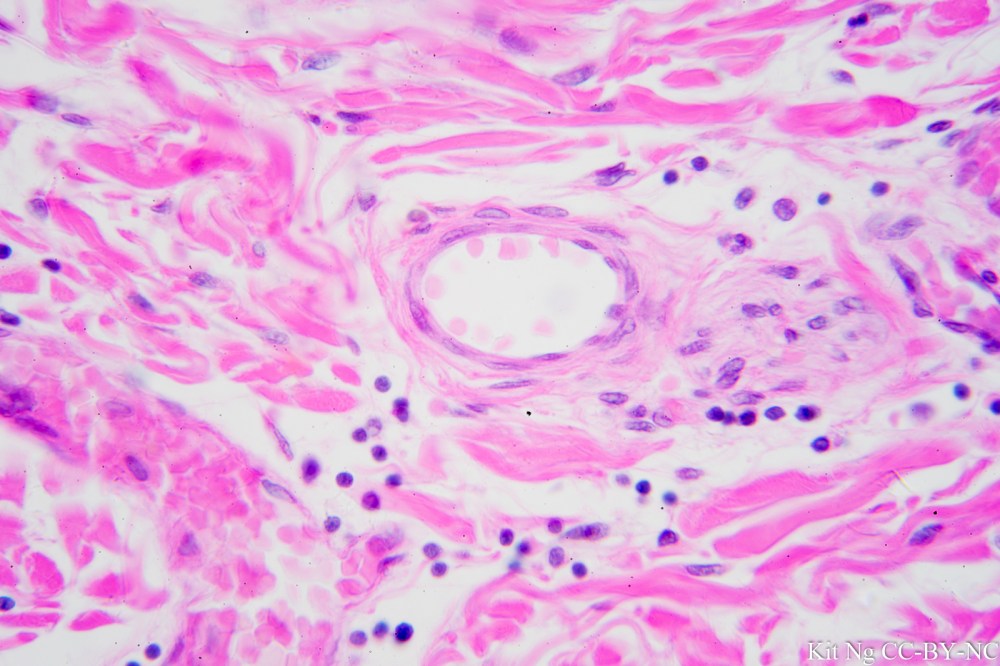

Kidney glomerulus.  Notice the space surrounding the structure in the middle is lined with a layer of flattened (squamous) cell.  (TM: 400x, picture taken with a Zeiss F40/0.65 on Sony NEX-6)